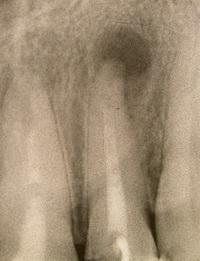

киста в челюсти причины